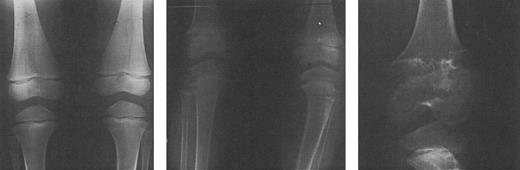

Adverse effects associated with deferoxamine include ocular and auditory abnormalities,225,227-235 sensorimotor neurotoxicity,236 changes in renal function,237,238 and pulmonary toxicity.239,240 A toxic manifestation of deferoxamine therapy of great concern in young children is failure of linear growth (Fig 7), associated with evidence of cartilagenous dysplasia of the long bones (Fig 8) and spine (Fig 9).141,142,241-247 Over the past 3 years, it has been recognized that short stature, primarily related to disproportionate truncal growth and loss of sitting height in thalassemic children,141,142 may be due to the effect of deferoxamine on spinal cartilage.244-246 At the same time, the findings of iron overload and hepatic damage in young transfused children outlined above have prompted our recommendations of the use of deferoxamine early in life, using reduced doses as a balance between risk and benefit. This practice is supported by studies of children who have received low-dose deferoxamine (15 to 35 mg/kg/night) since the age of 3 years, all of whom had normal sitting heights, standing heights, and normal spinal x-rays. By contrast, in a second cohort of children in which deferoxamine, administered at standard doses (50 mg/kg) from an equally early age had induced a comparable reduction in body iron burden, mean sitting height was markedly abnormal and significant x-ray abnormalities were observed.246 These data suggest that abnormal linear growth may be a direct toxic effect of prolonged administration of higher doses of deferoxamine, unrelated to changes in body iron. Because improvement in linear growth of patients with spinal abnormalities has not been observed even with reduction of deferoxamine dose, it would appear important to prevent this toxicity.

Radiographs of the femoral and tibial metaphyses of a child treated with deferoxamine therapy. Shown are the metaphyses prior to initiation of nightly subcutaneous deferoxamine (Fig 7A); 3 years after initiation of deferoxamine therapy (Fig 7B); and 6 years after initiation of deferoxamine therapy (Fig 7C). Radiographs show evidence of progressive widening and irregularity of the unossified metaphyseal matrix, which has irregular sclerotic margins. Similar processes in the proximal tibial metaphyses produced both varus and valgus deformities requiring bracing and osteotomy. (Reprinted with permission.144 )